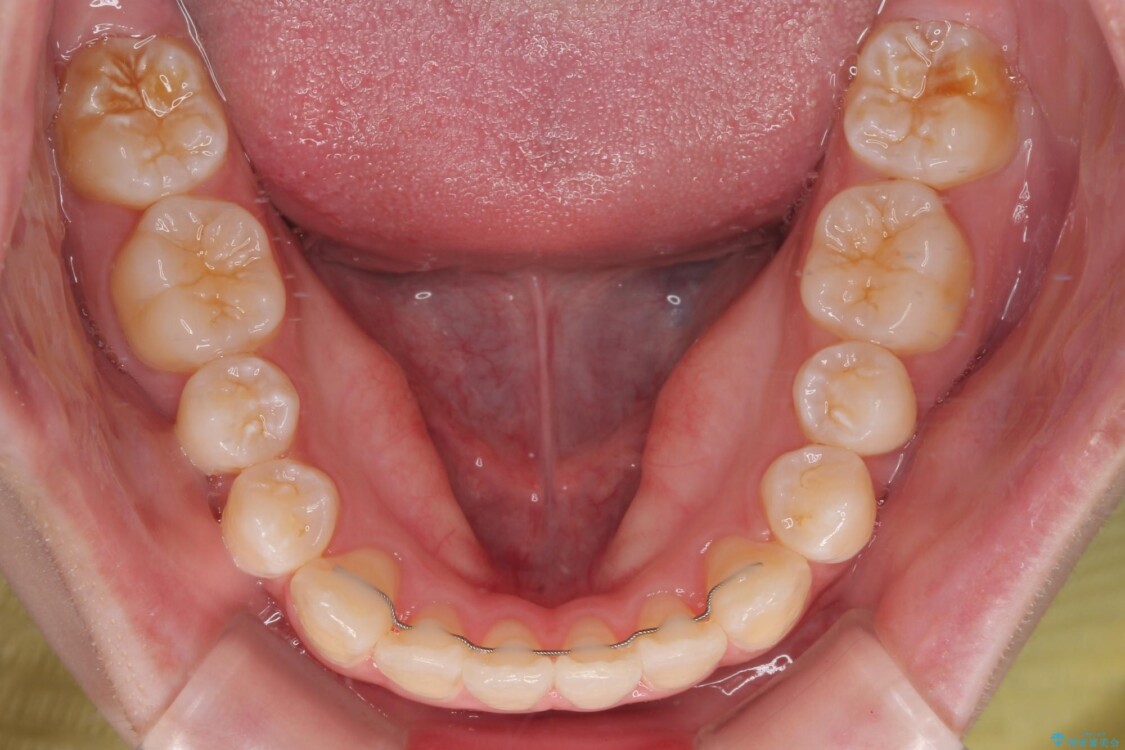

治療後

• 【モニター】前歯のデコボコをスッキリ解消!目立ちにくいワイヤー矯正でスピーディに治療完了 治療後画像